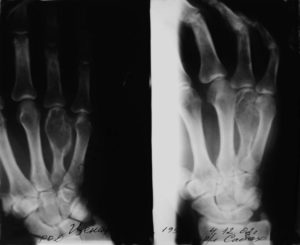

Диагностика энхондром, как правило, несложна. На рентгенограммах длинных трубчатых костей выявляется центрально расположенное облаковидное просветление. В зоне просветления могут обнаруживаться более темные участки – очаги кальцификации.

Опухоли в области коротких трубчатых костей обычно выглядят однородными и занимают большую часть поперечника или весь поперечник кости. Кортикальный слой не нарушен.

Энхондрома — опухоль, располагающаяся внутри кости. В центре вздутого одиночного очага располагается гомогенное просветление неправильной округлой или овальной формы с чёткими контурами. На его однородном фоне обнаруживают единичные тени очагов обызвествления хряща.

Рентгенологически энхондрома представлена очагом просветления, локализованным в метафизарном и (или) диафизарном отделе кости, с наличием истончения, либо вздутия кортикальных слоев кости на уровне поражения, а так же очагов оссификации внутри опухоли.

Рентгенологический снимок предоставляет самую точную информацию об опухоли. Так на рентгенограмме энхондромы имеют вид маленьких светлых пятен, располагающихся в середине кости. Площадь их не превышает пяти сантиметров. Если в области опухоли просматривается рисунок в виде арок или колец, это подтверждает наличие в ней хрящевой ткани.

Отсутствует нормальный костный рисунок в области метафизов, а вместо него определяется неравномерное просветление. Истончается корковый слой. На рентгенограмме стоп и кистей видно деформация фаланг и ее укорочение. Просветления наблюдаются в центральном отделе, обычно корковый слой остается без изменений.